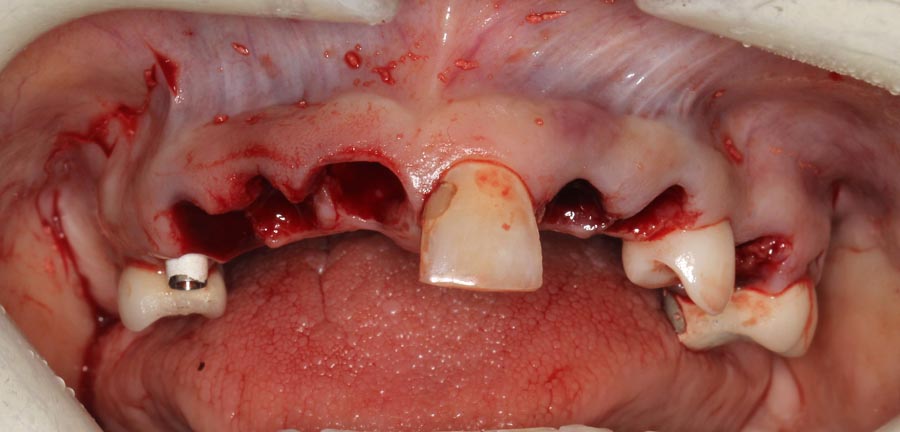

Smile GalleryImplant RestorationsFull Mouth Implant Restoration Full arch zirconia implant bridge (full smile) 1 of 37 Pre-op full smile Pre-op lips retracted Pre-op panoramic x-ray Extraction of strategic teeth Placement of implants Extraction of some remaining teeth after verification of adequate implant stability Occlusal view Post-op panoramic x-ray Immediately fabricated provisional restoration (tissue side view) Immediately fabricated provisional restoration (occlusal side view) Immediate provisional delivered on day of surgery Immediate provisional 2 weeks later Scalloped tissue developed from the provisional at 2 weeks Jig used for making a master impression Provisional in place (full smile) Provisional in place (lips retracted) Provisional in place (right side) Provisional in place (left side) Wax try-in (full smile) Wax try-in (right side full smile) Wax try-in (left side full smile) Wax try-in (full face, lips together) Wax try-in (full smile) Wax try-in (right side) Wax try-in (left side) Wax try-in (lips retracted) Full arch zirconia implant bridge on master cast (frontal view) Full arch zirconia implant bridge on master cast (occlusal view) Implant positions and soft tissue representation on master cast (occlusal view) Soft tissue representation on master cast (frontal view) Full arch zirconia implant bridge (tissue side view) Soft tissues on day of delivery (occlusal view) Soft tissues on day of delivery (frontal view) Full arch zirconia implant bridge delivered (lips retracted) Full arch zirconia implant bridge (lips retracted, close up) Post treatment panoramic x-ray Full arch zirconia implant bridge (full smile)